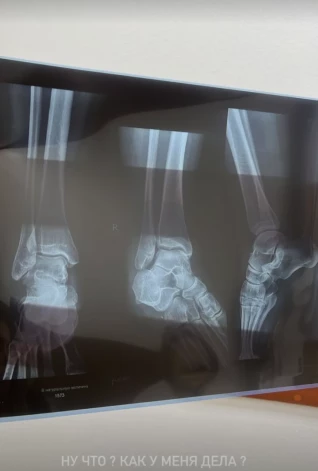

В итоге Анна все-таки отправилась в травмпункт, чтобы сделать рентген. В личном блоге она выложила кадры из медицинского кабинета.